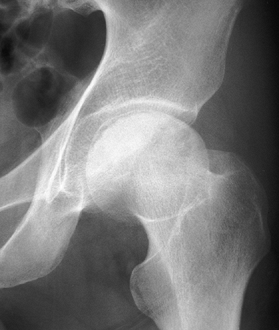

Figure 125.13.

Stage IV osteonecrosis. Marked flattening of the femoral head is present without radiographic evidence of acetabular involvement. |

Figure 125.14.

Stage V osteonecrosis. The femoral head is markedly flattened. The joint line is narrowed, and the acetabulum shows irregularity, sclerosis, and radiolucency. |

Figure 125.15.

Stage VI osteonecrosis showing advanced degenerative changes that have taken place in the hip joint secondary to osteonecrosis of the femoral head, treated by intertrochanteric osteotomy. |